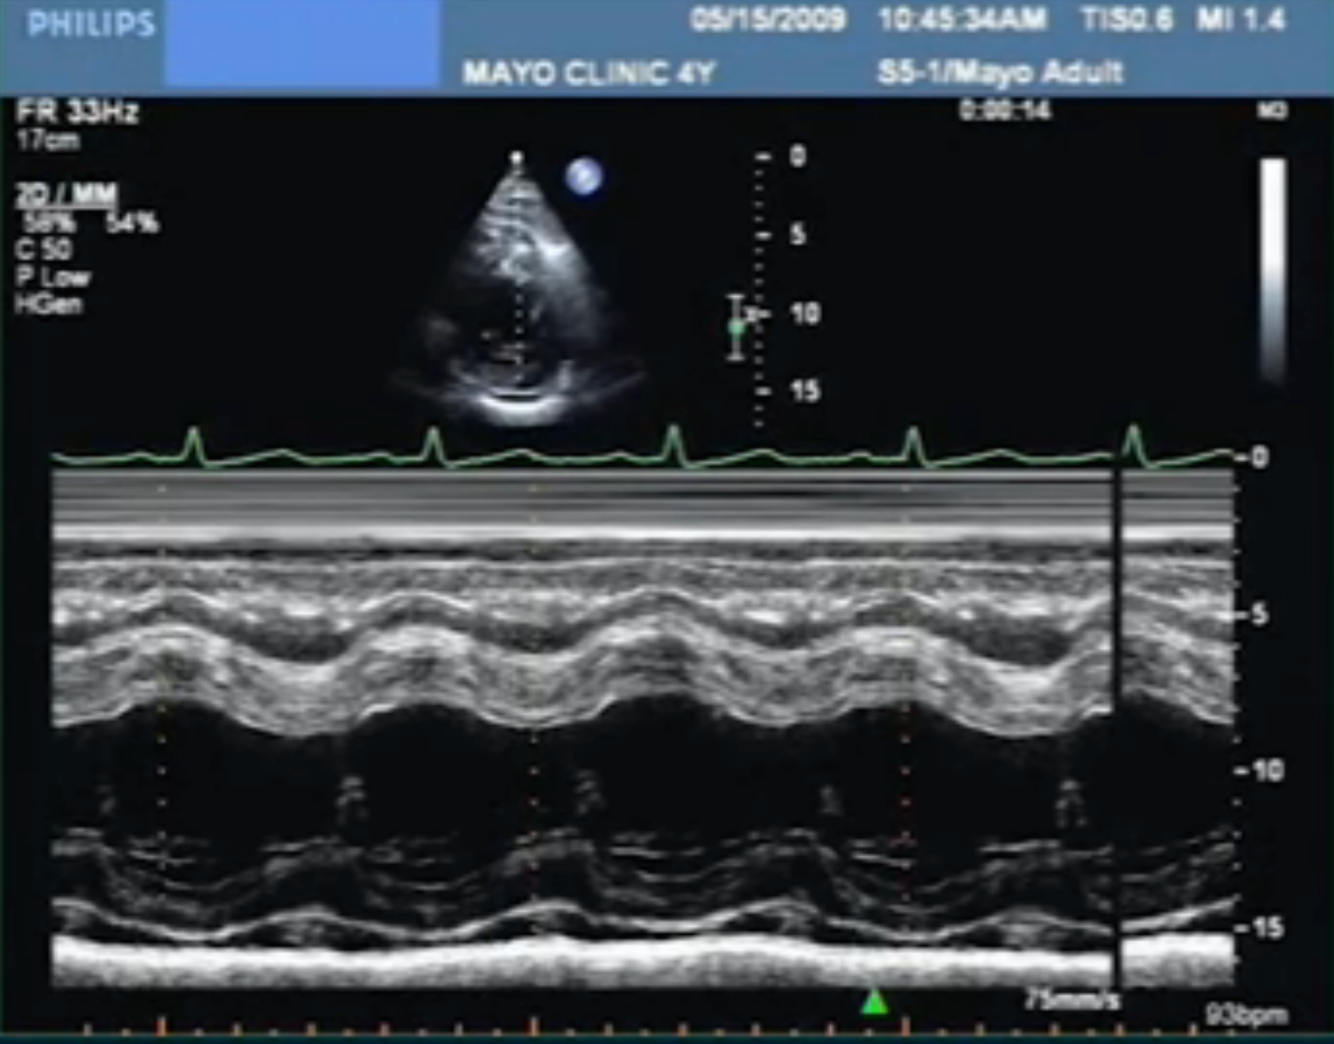

Diagnosis?

Perforated MV leaflet (*clue is to see the PISA off the midline)